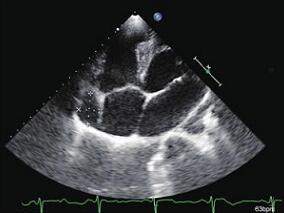

1小时条评论病例摘要 男性,28岁。主因发作性心悸、气短2年余,加重3天入院。 现病史 2年前患者每于劳累休息欠佳、饮酒后出现心悸、气短,最长持续约1小时,发作时伴大汗,无发热、寒战,无恶心、呕吐,无肩背部放射痛,无咽部紧缩感等特殊不适。2年间不规律发作共计7次,未予诊治。3...